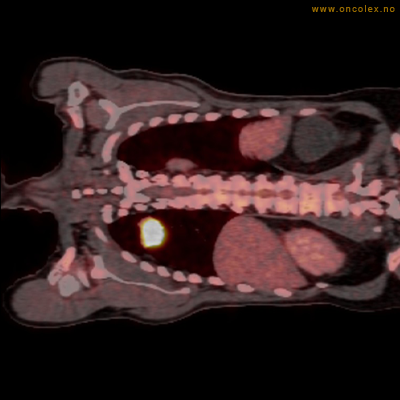

Eksempler på funn

Vev som tar opp mer radioaktivt stoff, synes som hvite områder som lyser opp mer i forhold til annet vev som tar opp mindre sukker.

Høyt opptak av 18F-FDG i adenokarsinom i rektosigmoideumovergangen. Fysiologisk opptak i blæren.